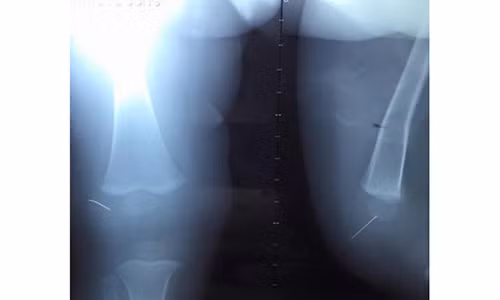

| Phim chụp ½ kim khâu dài 3cm mắc kẹt trong khớp gối của cháu Toàn. |

“Tôi cố gắng rút kim ra khỏi cơ thể con trai nhưng không được, chiếc kim đã bị gãy và nửa đầu của chiếc kim khâu diều đã mắc kẹt trong khớp gối của cháu. Ngay lập tức, gia đình đã đưa cháu toàn đến Bệnh viện Nhi Trung ương để thăm khám và điều trị” – Mẹ cháu Toàn cho hay.

Thạc sĩ, bác sĩ Lê Tuấn Anh – Khoa chỉnh hình nhi (BV Nhi Trung ương) – người trực tiếp phẫu thuật cho cháu Toàn chia sẻ, khi tiếp nhận cháu Toàn, bệnh viện đã tiến hành chụp phim, làm các xét nghiệm và chỉ định phẫu thuật.

Không ngoài dự đoán, khi tiến hành phẫu thuật khớp gối gắp đoạn kim 1,5cm cho cháu Toàn, các bác sĩ không thấy dị vật trong khớp gối. Do đó, các bác sĩ đã sử dụng máy X – quang tăng sáng, hỗ trợ định vị dị vật và phát hiện đoạn kim đã găm vào xương bánh chè của cháu.

“Phải mất hơn 1 giờ đồng hồ, chúng tôi mới gắp được đoạn kim khâu 1,5cm ra khỏi cơ thể trẻ. Hiện nay, cháu Toàn vẫn đang được các bác sĩ chuyên khoa Chỉnh hình chăm sóc và theo dõi” – Ths Tuấn Anh nói.